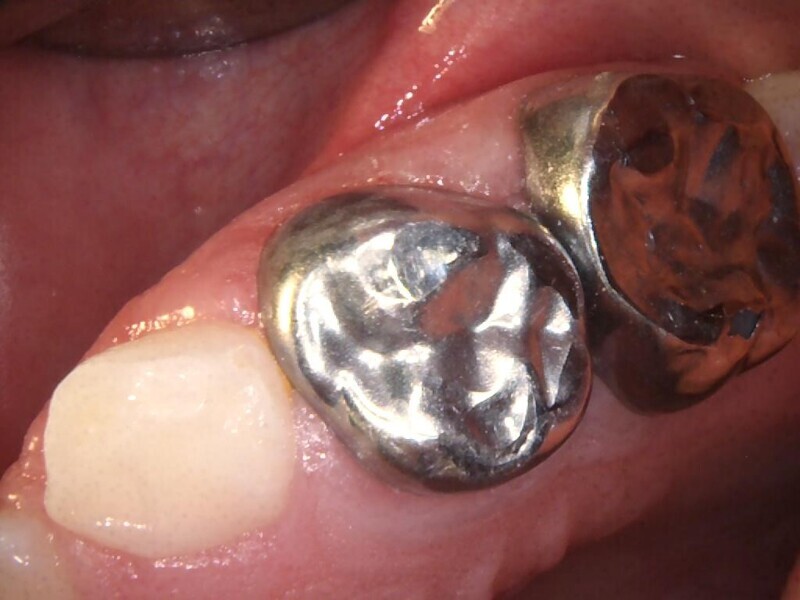

Cas 1 (Figs 1-4)

Cette patiente âgée de 4 ans et 7 mois présentait une douleur qui affectait la seconde molaire temporaire inférieure droite depuis plusieurs jours. L’examen clinique a révélé un gonflement du versant vestibulaire de la gencive et un œdème facial, ainsi qu’une carie occlusale profonde.Un diagnostic de nécrose pulpaire et d’abcès apical symptomatique ayant été posé, un traitement a été prescrit à la patiente, afin de maîtriser l’infection aiguë, et un nouveau rendez-vous a été fixé après l’antibiothérapie. Lors du deuxième rendez-vous, elle ne présentait plus aucune douleur et l’abcès buccal s’était partiellement résorbé. Il a été décidé de procéder à une pulpectomie et à la restauration de la dent. Dans ce cas, la dent présentait une extrusion excessive de matériau d’obturation. Après 15 mois, la réévaluation a confirmé l’absence de signes cliniques ou radiologiques pathologiques, et une apposition osseuse était visible dans la zone de la furcation.